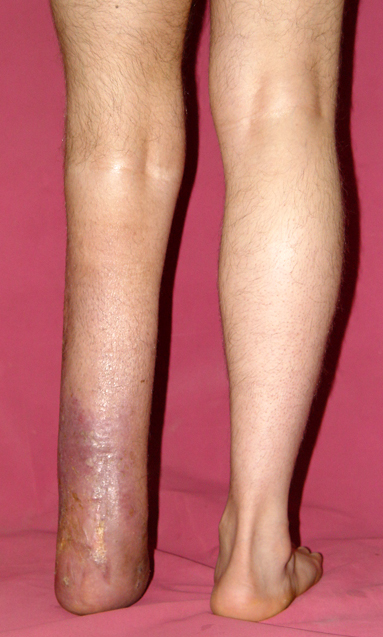

3. POSTTRAUMATIC LOWER LIMB SHORTNESS (MALUNION)

This type of shortness occurs after a fracture heals in a shortened position. Most cases are seen in adults and can be treated with one lengthening operation. Additional deformities can be corrected simultaneously. Most of these cases can be treated with lengthening over nail or just corrections and intramedullary nailing.